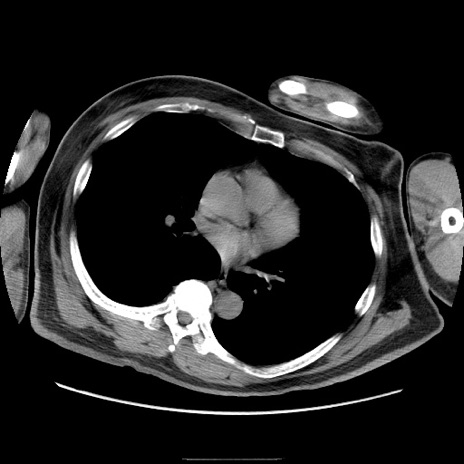

冠状断像

【症例】50歳代男性

【主訴】腹痛

【現病歴】AVMからの被殻出血のため回復期リハ病棟入院中。 本日午後3時頃急に下腹部痛が出現した。

【既往歴】AVM、被殻出血、虫垂炎、高血圧

【身体所見】意識晴明、左半身不全麻痺、会話の理解は良好、36.5°C、腹部:膨隆、全体に板状硬、下腹部正中に圧痛点あり、反跳痛-、筋性防御不明、右下腹部にope scar

【データ】WBC 9400、CRP 0.06